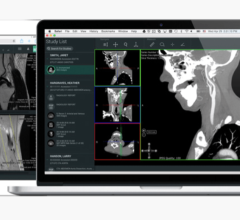

March 24, 2014 — Medical physicists met in Denver, Colo., March 15-18 for the American Association of Physicists in Medicine (AAPM) Spring Clinical Meeting, hosted at the Denver Marriott Tech Center. The meeting focused on helping medical physicists with the integration of emerging technologies into the clinical environment. Mirada Medical demonstrated its comprehensive suite of advanced deformable image registration (DIR) software tools to meeting attendees. The company utilizes its scientifically advanced DIR algorithms to provide practical tools to support treatment planning.

Mirada’s scientists have made their algorithms application and modality specific — carefully tuning internal parameters, such as deformable field smoothness, degree of freedom and similarity function sensitivity. This provides a strong basis for multi-modality contouring, auto contouring, dose deformation and composite dose, and it provides support for adaptive therapy and re-treatment decisions.